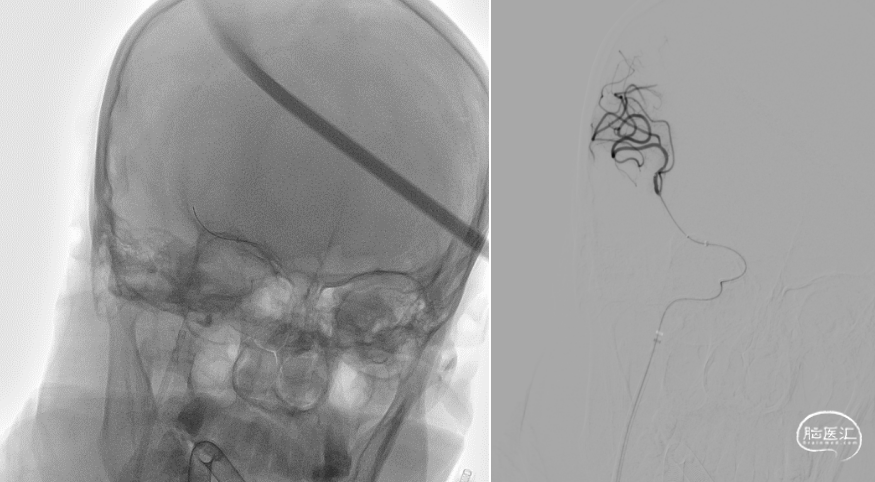

术前造影提示右侧大脑中动脉下干闭塞。

使用8F导引导管在6F 125cm Tethys®中间导引导管同轴下超选至右侧颈内动脉建立通路,造影可见右侧大脑中动脉M1下干闭塞。

Tethys®中间导引导管到达大脑中动脉血栓部位,边抽边撤Tethys®中间导引导管,未见血栓;Tethys®中间导引导管再次到位大脑中动脉,微导丝微导管通过闭塞段,微导管造影证实在真腔。

释放3*25mm Syphonet®取栓支架,停留5分钟后撤出Syphonet®取栓支架并保持负压抽吸,第一次复查造影血流未通。

再次重复上述操作,释放Syphonet®取栓支架并停留5分钟后撤出取栓支架并保持负压抽吸,再次复查造影右侧大脑中动脉下干血流恢复,mTICI血流3级。